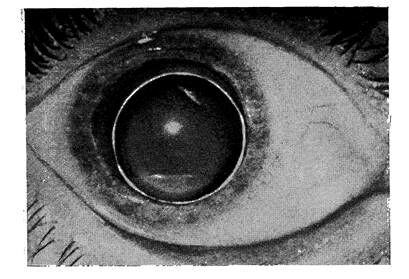

Кератоконус. Кератоконус – состояние роговицы, при котором значительно изменены ее форма и кривизна (рис. 1).

Рис.1.

Кератоконус.

При этом конусообразно выступает преимущественно ее центральная часть. Наличие такой аномалии следует предположить в тех случаях, когда обнаружено снижение остроты зрения у детей с прозрачными преломляющими оптическими средами и нормальным глазным дном. В таких случаях необходимо определить форму, кривизну и рефракцию роговицы (кератометрия, офтальмометрия, рефрактометрия). При этом всегда выявляют выраженный астигматизм, чаще неправильный. Кератоконус нередко имеет злокачественное течение, т.е. его степень увеличивается, а главное возникает и прогрессирует помутнение роговицы и одновременно резко падает зрение.